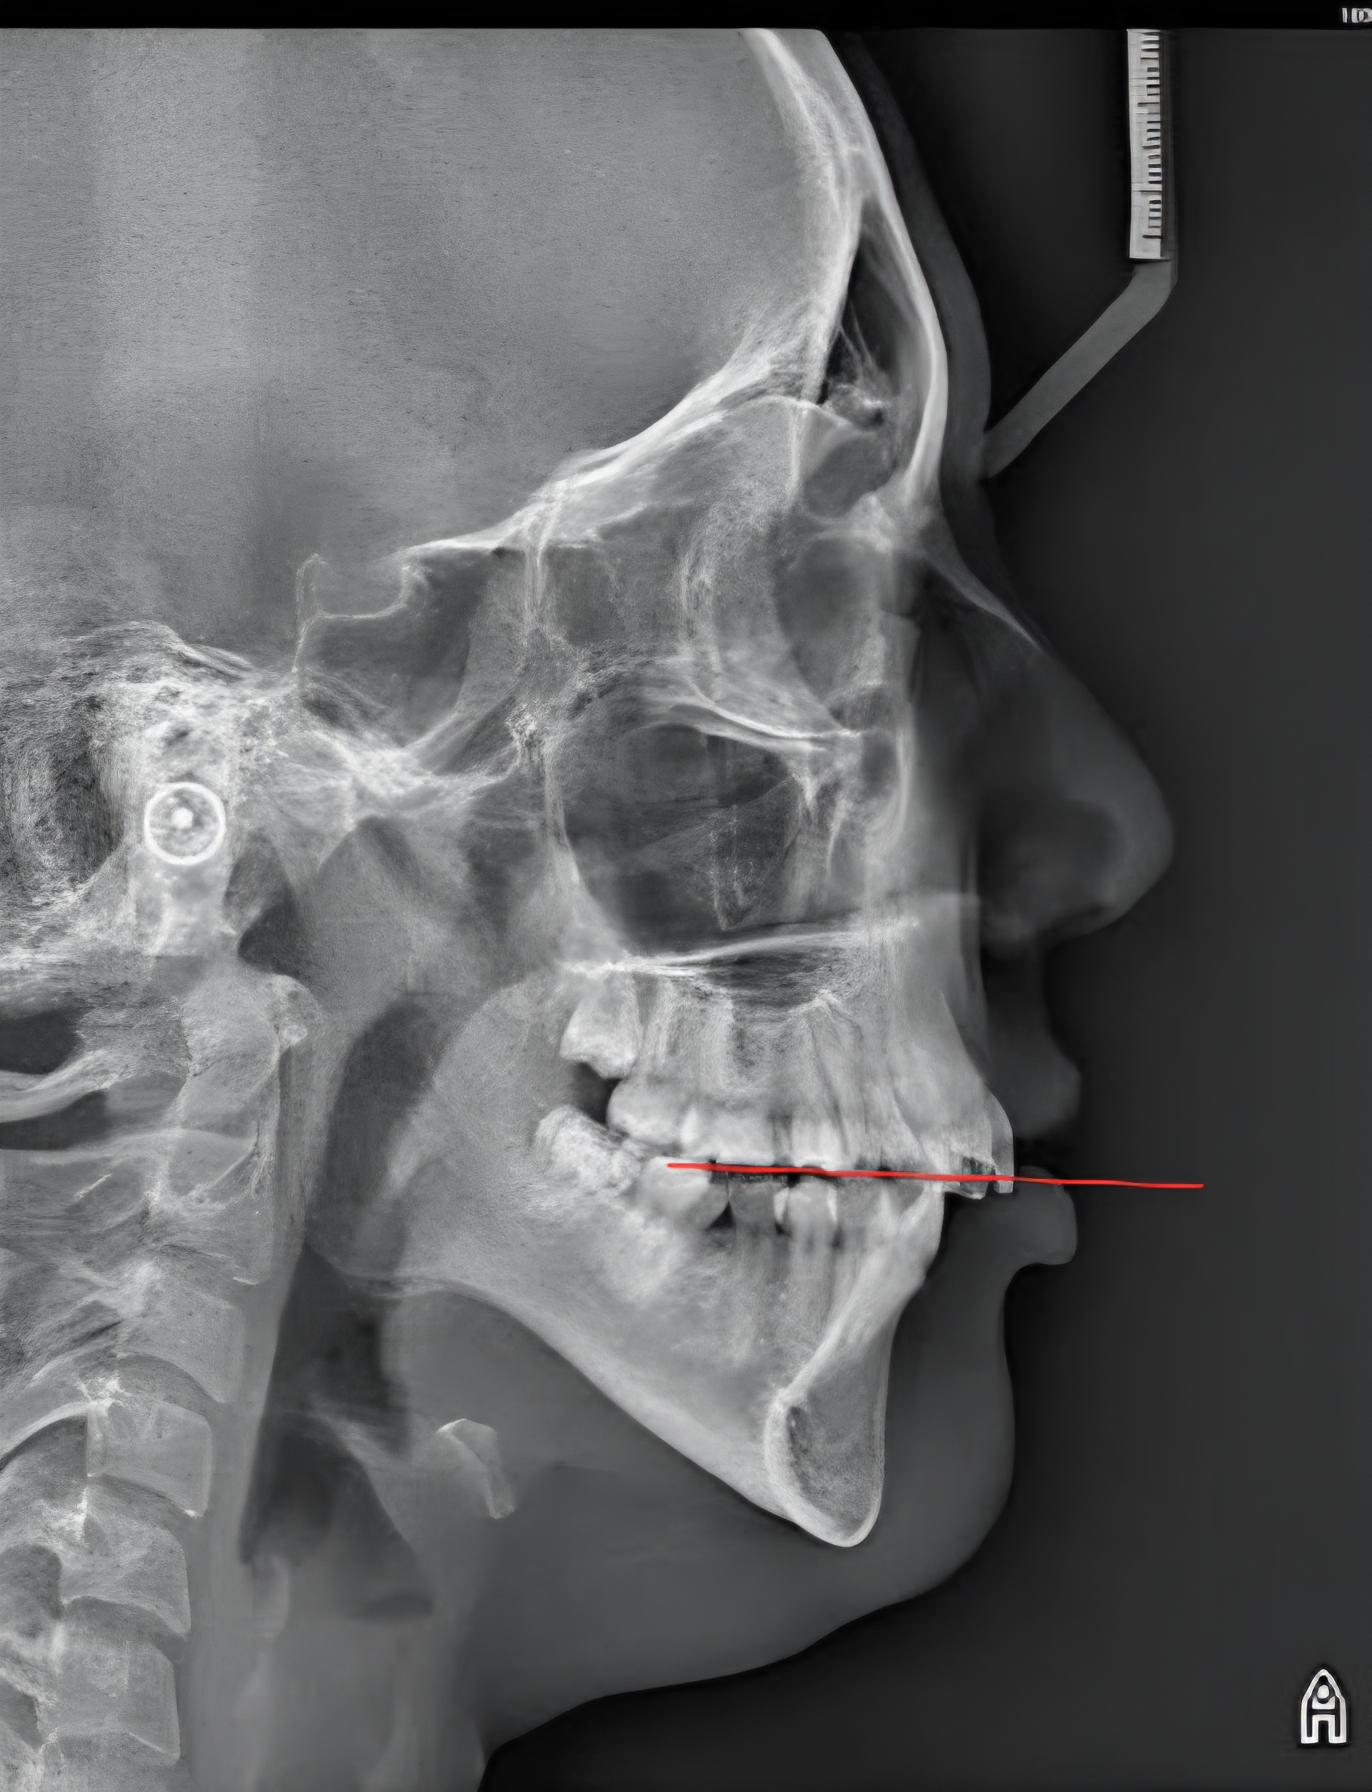

The mandibular plane angle here is too high closely related to the occlusal plane which is NOT what you want